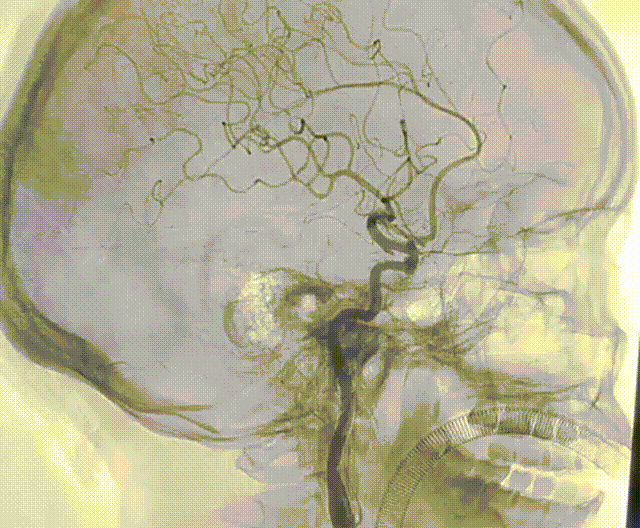

通桥麒麟™血流导向密网支架完全释放后造影,支架贴壁良好,位置可。

通桥麒麟™血流导向密网支架完全释放,造影示动脉瘤内造影剂滞留明显。

通桥麒麟™血流导向密网支架完全释放,全脑血管造影。